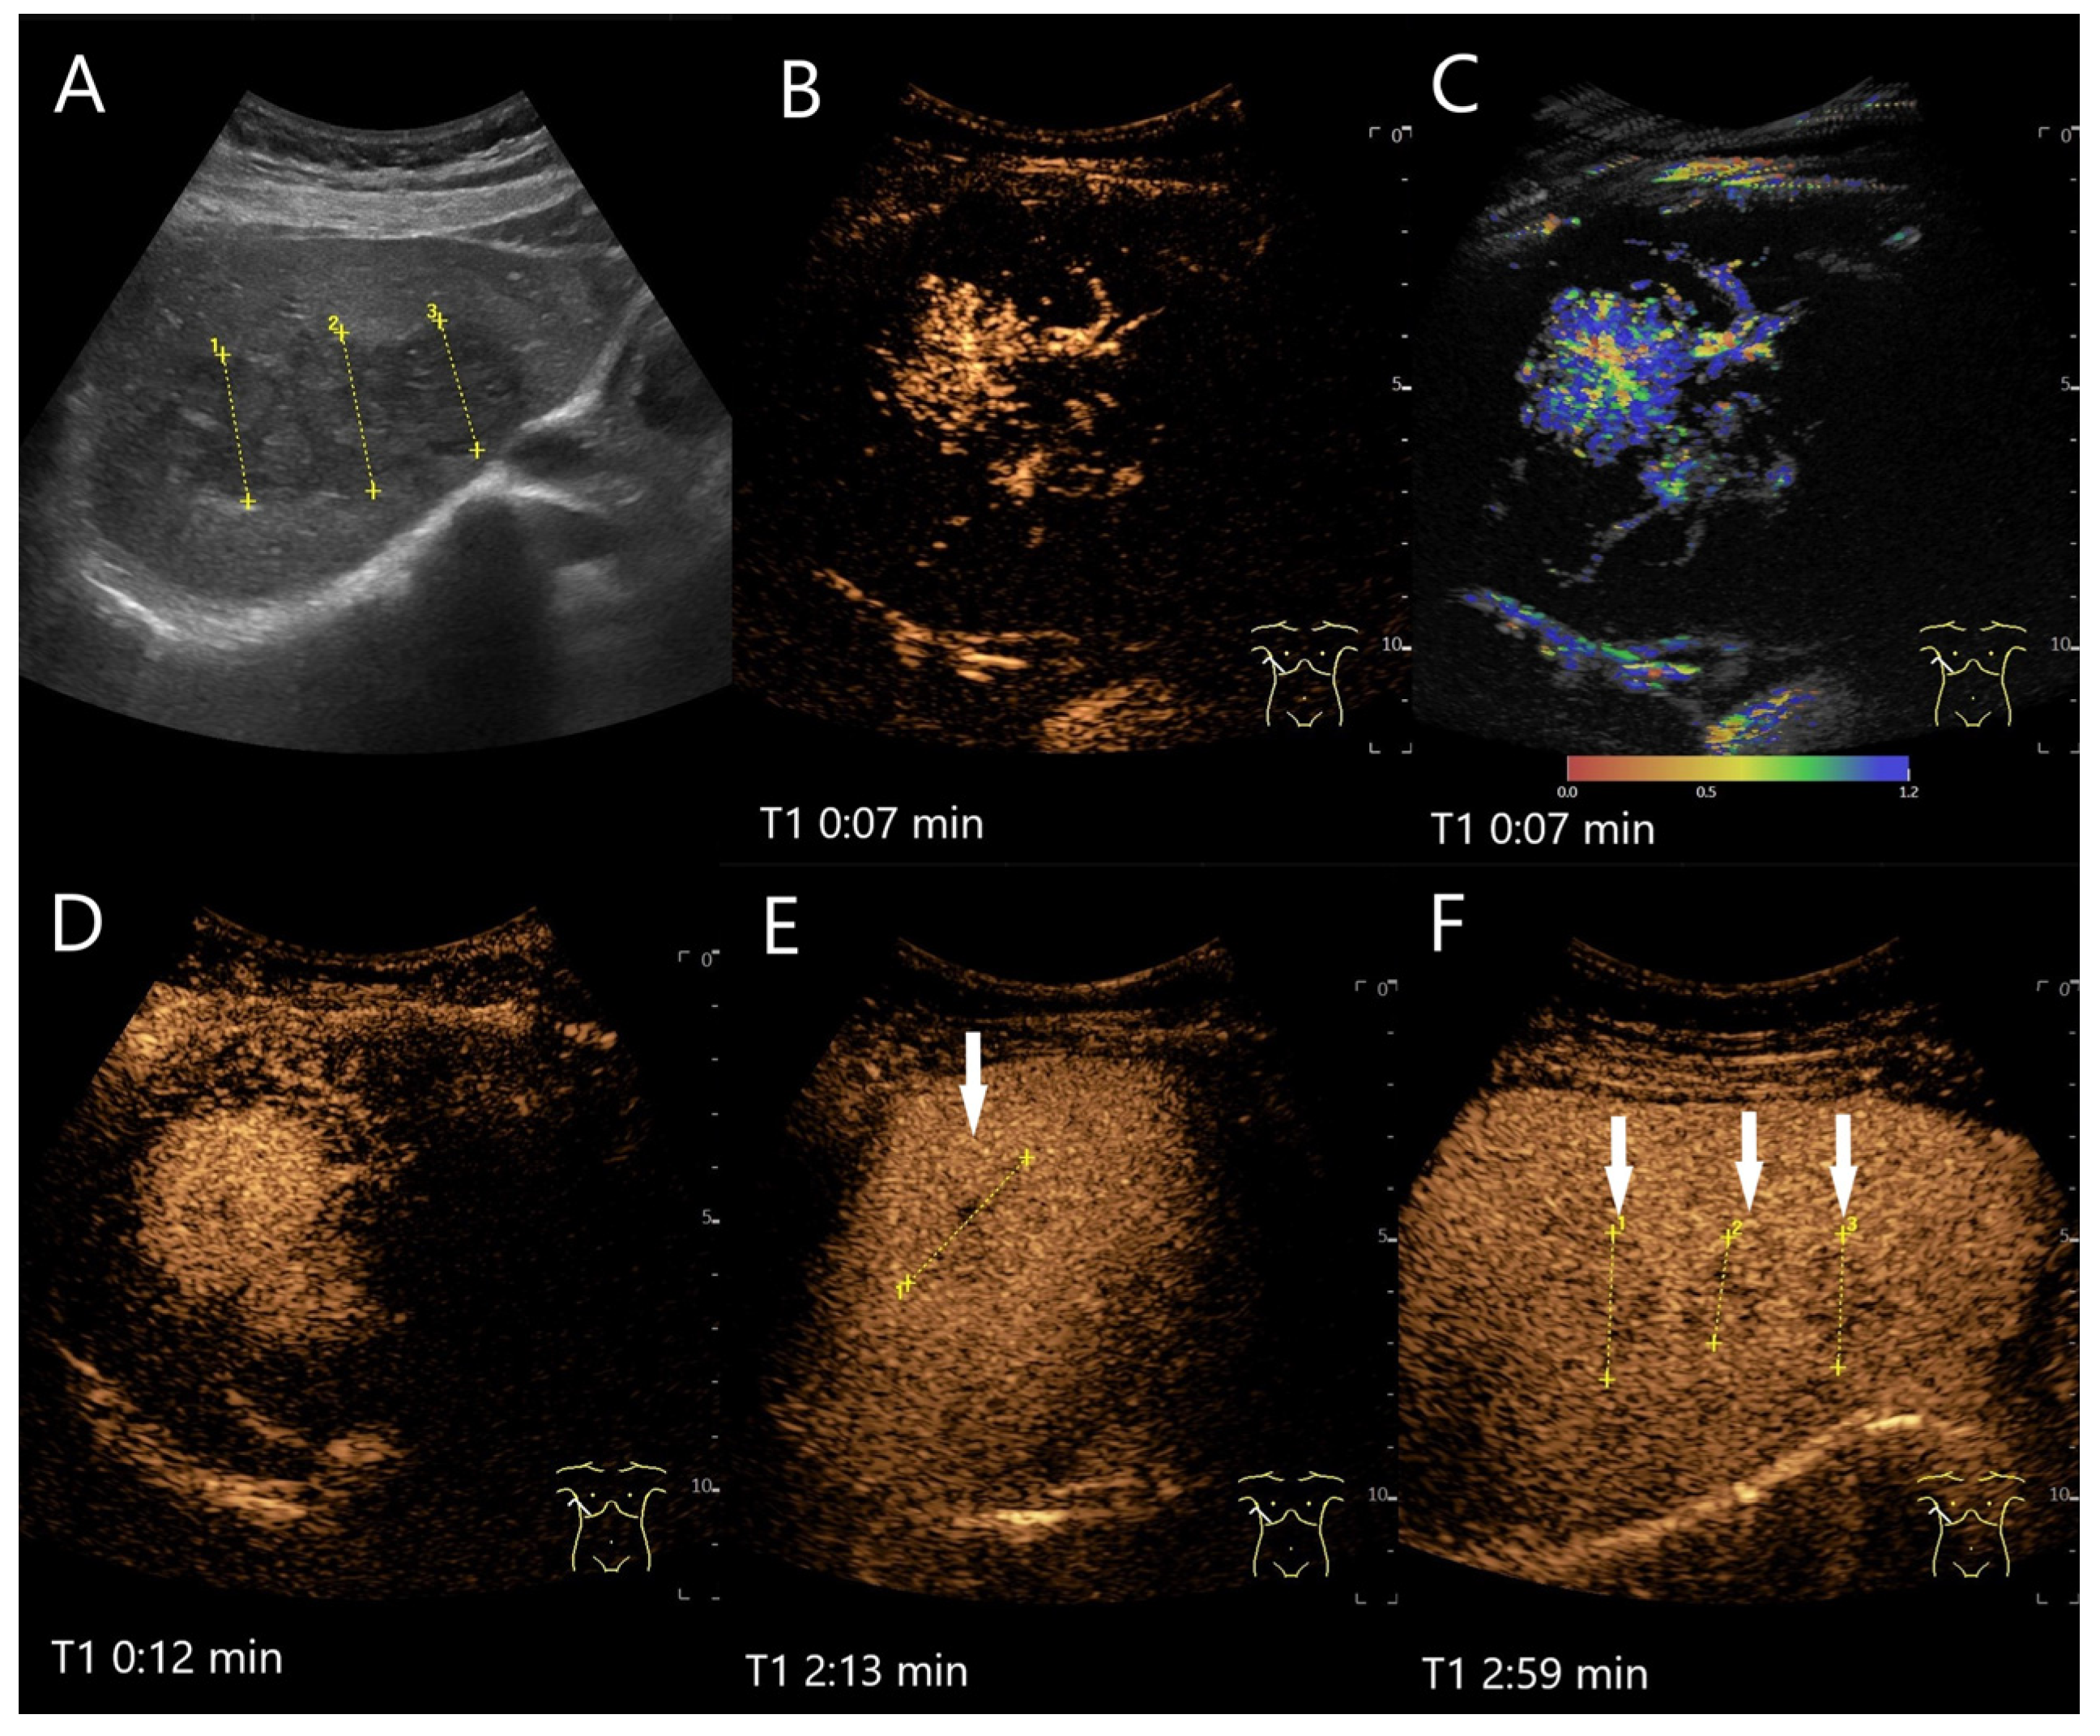

Figure 5.

FNH/nodular regenerative hyperplasia newly diagnosed in follow-up care after colon carcinoma and adjuvant chemotherapy with capecitabine and irinotecan. Initially, the lesions with a size up to 30 mm showed a wheel-spoke-like homogeneous hyperenhancement in the AP with isoenhancement in the PVP and LP. Over time, however, hypoenhancement developed in the LP. The images show the lesions three years after the initial diagnosis: the lesions (between the markings) are slightly larger (A). CEUS (B) and parametric imaging (C) show a typical wheel-spoke-like enhancement. In parametric imaging (C), the time of enhancement is displayed in different colors. The lesion is homogeneously hyperenhanced in the AP, a central scar is visible (D). In the LP, the lesions (arrows) are hypoenhanced with emphasis on the central parts (E,F). These lesions were, therefore, not clearly classifiable as benign, particularly in a patient with a history of colon carcinoma. A US-guided biopsy is performed. This revealed findings compatible with FNH and no evidence of metastases.